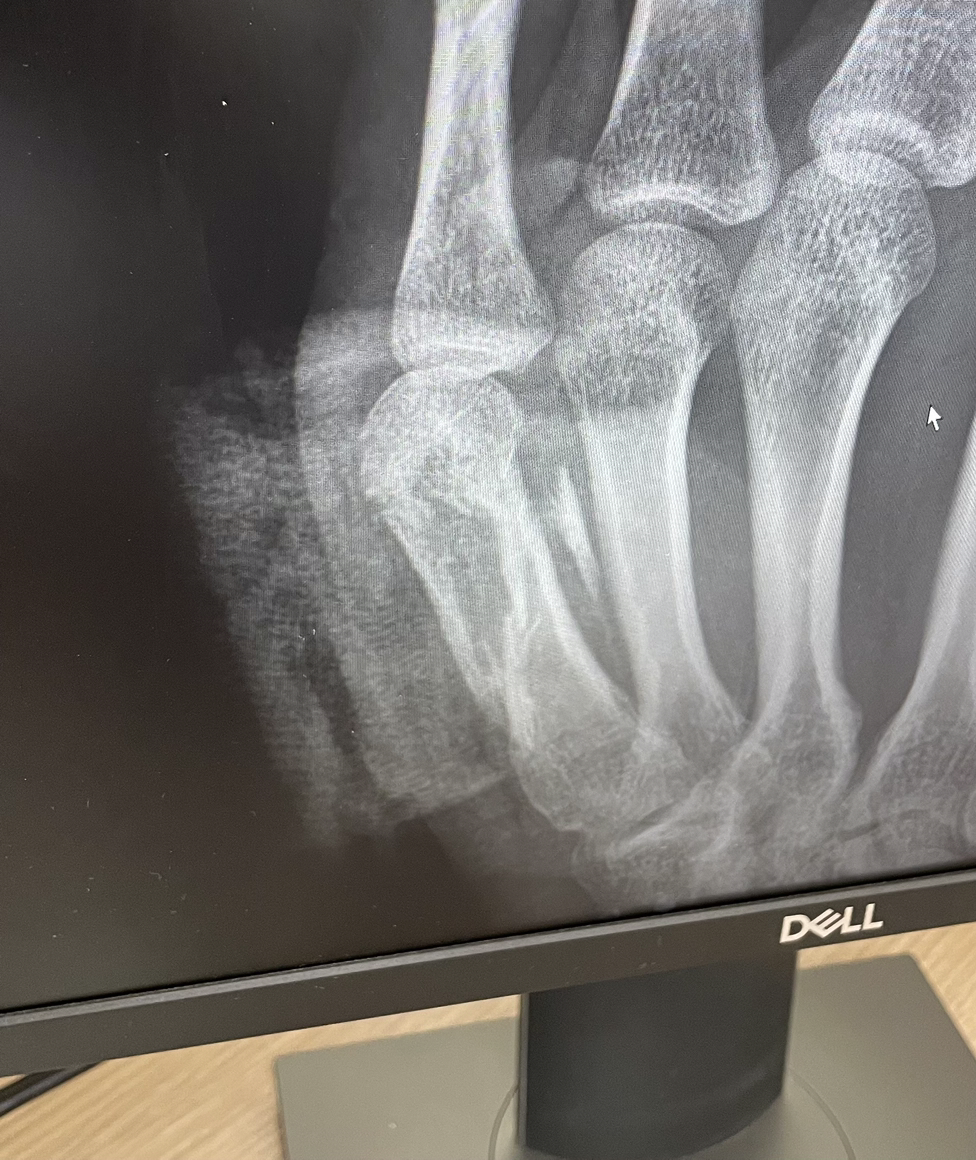

아래 사진은 심신미약자는 보지 않은 걸 권고한다.

좌측: 뼈가 제자리에 있지 않은 상태에서 붙고 있다